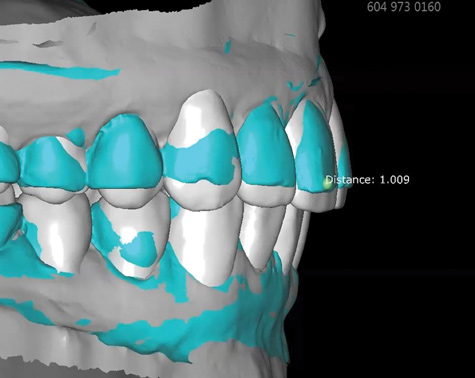

Fig 8. Scans used to mock-up desired restorative result using modeling software. The teal-green areas represent the current tooth form, and the white areas show the desired or digital wax-up. A reduction of 1.009 mm was required prior to preparation, making endodontic treatment likely if orthodontic treatment is not considered.

Figure 8

Fig 9. Scans used to mock-up desired restorative result using modeling software. The teal-green areas represent the current tooth form, and the white areas show the desired or digital wax-up. A reduction of 1.009 mm was required prior to preparation, making endodontic treatment likely if orthodontic treatment is not considered.

Figure 9